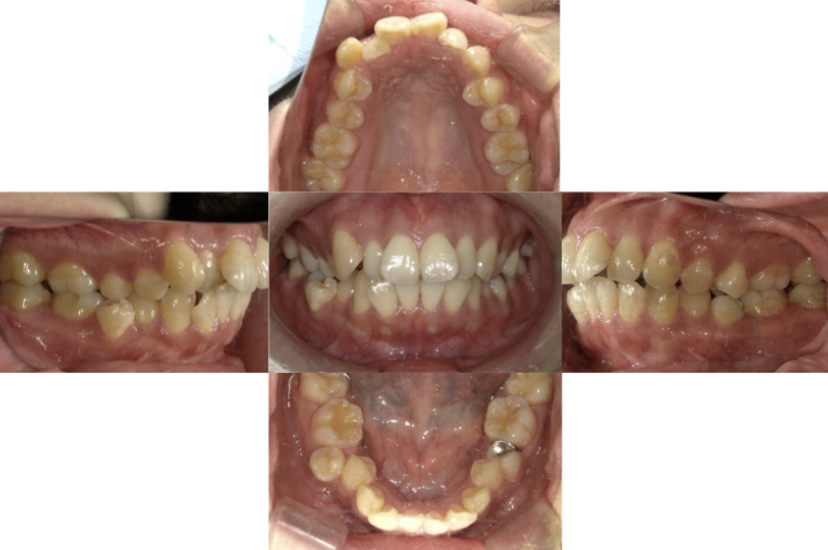

BEFORE

AFTER

症例4

下顎前突、叢生

抜歯

ブラケット矯正

上下顎叢生、反対咬合(上下の前歯のガタガタ、若干受け口)のケースです。

装置はラビアル(上下表側)で、上下顎の小臼歯を4本抜歯を行っています。抜歯したスペースを使って、上下の叢生改善と前歯の受け口の改善を行っています。

主訴 前歯のガタガタを治したい。

年齢・性別 45歳 女性

お住まいの地域 神奈川県川崎市

治療方針 抜歯スペースを利用して上前歯の叢生(ガタガタ)の改善と受け口の改善

抜歯部位 上顎左右第一小臼歯、下顎左右第二小臼歯

使用装置 ラビアル(上下表側)、顎間ゴム

治療期間 2年6か月

治療回数 20回

リテーナー クリアリテーナー